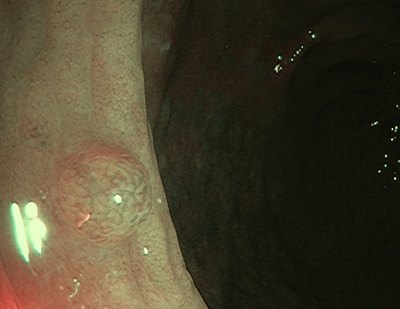

1 тип — характерний для гіперпластичного поліпа

Судини: світліші або схожі на навколишні

Поверхня: круговий візерунок з дрібними крапками — візерунок із темнішою ділянкою в центрі, оточений світлішою слизовою оболонкою